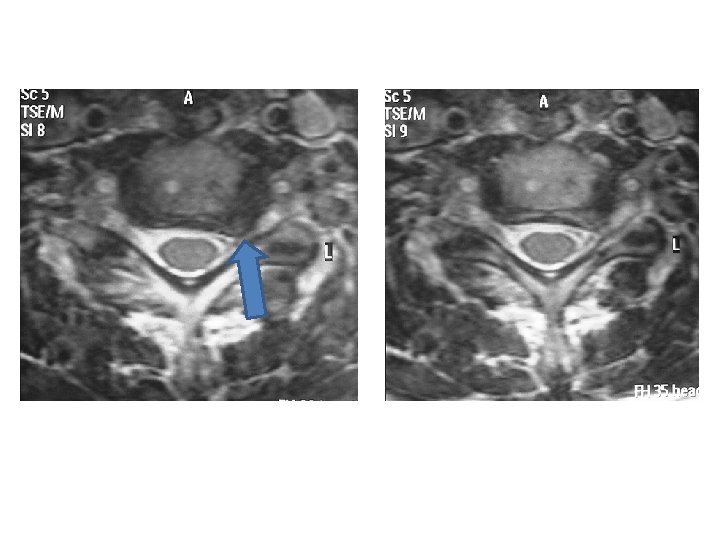

IRM en T 2 coupes axiales

Cas clinique 1 • Examens complémentaires: – EMG résultat: atteinte neurogène C 7 gauche – Analyse de l’IRM: discopathies multiples , déshydratation des disques, déformation rachidienne, conflit disco radiculaire foraminal C 7 gauche • Propositions de prise en charge?